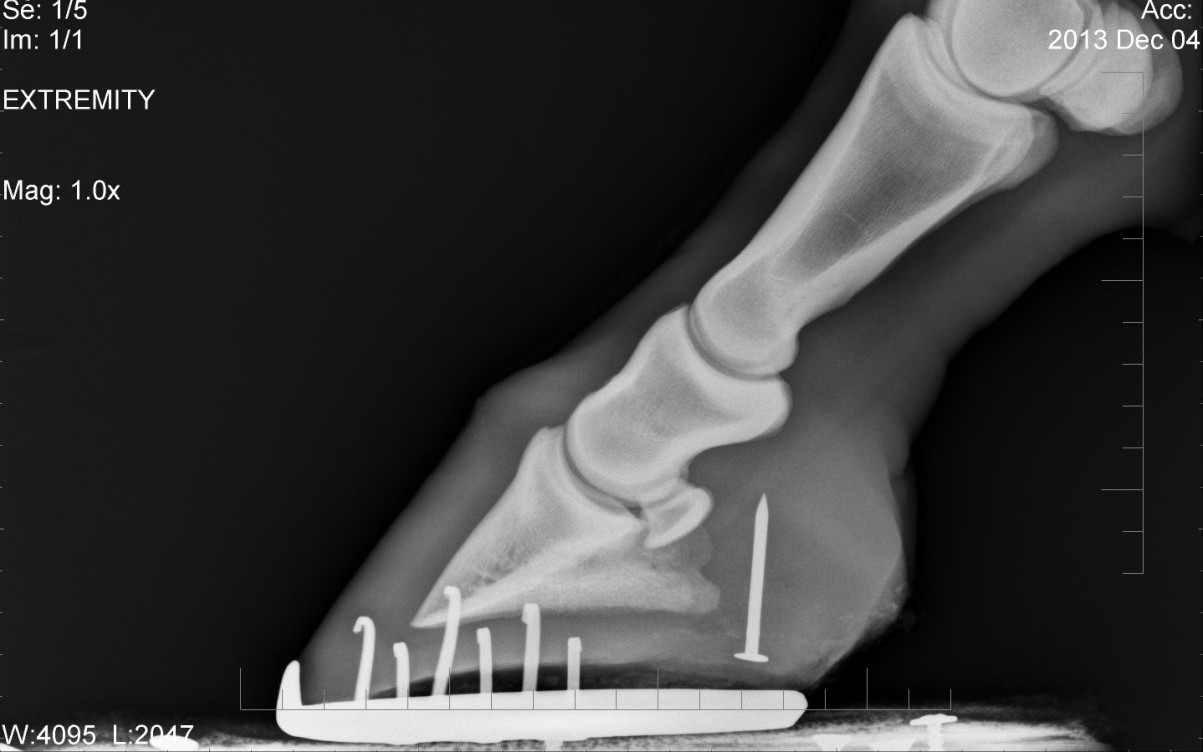

From www.burwashequine.ca

Luke Puncture Wound from a Nail in the Foot — Burwash Equine Services First Aid For Nail Puncture In Foot First aid for a puncture wound is fairly simple, and most of it you can do yourself. Depending on when your last tetanus shot was, a doctor may recommend getting a booster shot within 48 hours of a nail puncturing your skin, especially if the. Not only will this make moving. Keep in mind, however, that depending on what you. First Aid For Nail Puncture In Foot.